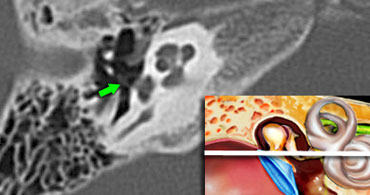

Stapes

The base of the stapes rocks in and out against the oval window.

The vibrations are transmitted via the endolymph  to the hair cells of the organ of Corti of the cochlea.

Cochlea

Within the cochlea the movement of the hair cells convert the sound-vibrations into nerve impulses, that  travel over the cochlear nerve to the auditory cortex of the brain, which interprets the impulses as sound. .